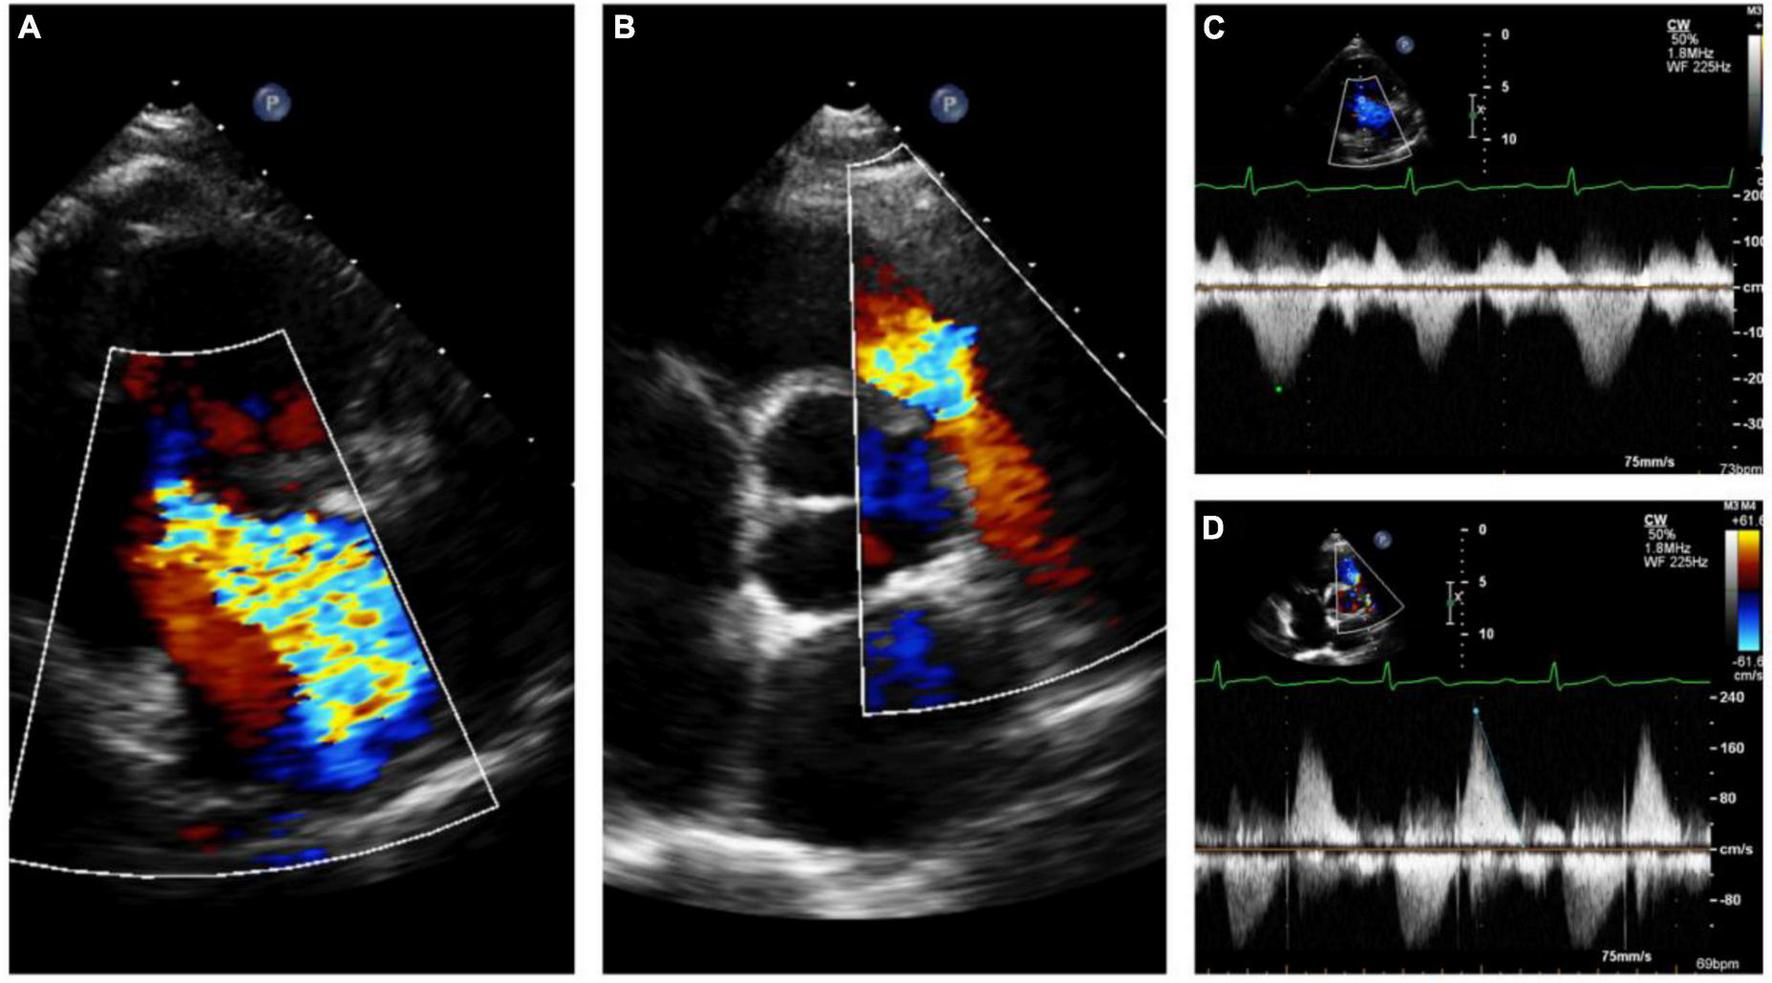

FIGURE 6

Echocardiography monitoring in carcinoid heart disease (CnHD): Pre-surgical baseline echo. Severe tricuspid regurgitation (A) with pulmonary valve stenosis (B) with corresponding continuous wave Doppler (C, D).